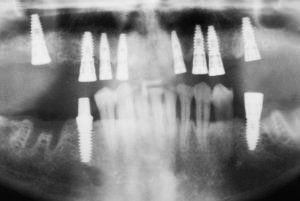

At Dental Innovations in Wasilla, AK, we can fit the very latest implant supported dentures, implant retained dentures, or more complex or targeted solutions for a particular patient situation. Contact our team today to arrange a consultation.